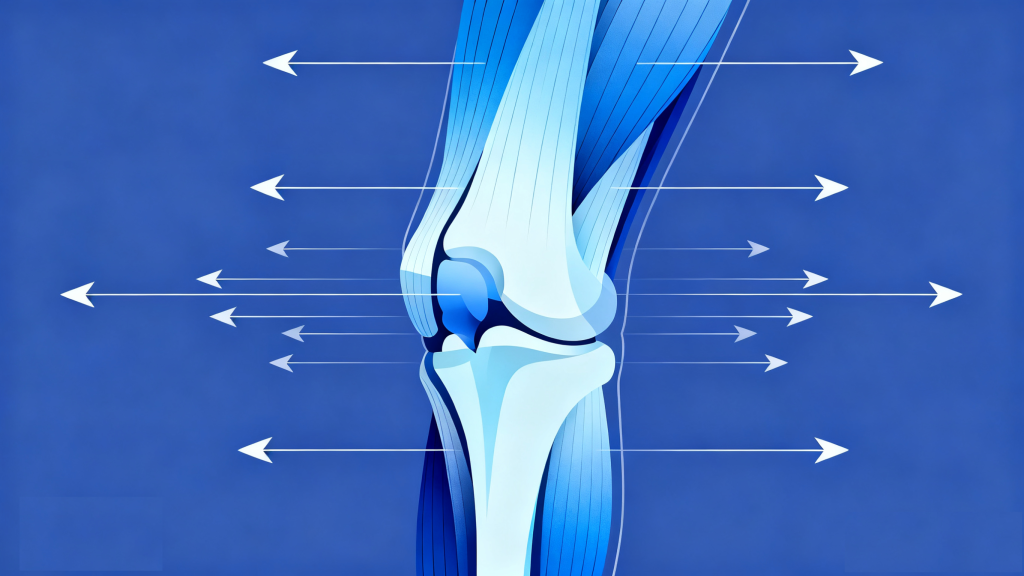

很多人认为“跑步伤膝”是因为跑步时膝关节承受的压力大,但实际上,人体膝关节的软骨和韧带本身就具备一定的承重和缓冲能力。真正导致“跑步膝”的,往往是不当的运动习惯或自身条件的短板,主要包括以下几方面:

错误的跑步姿势:这是最常见的诱因。比如落地时脚腕过度内旋或外旋、膝盖内扣、身体前倾过多,会导致膝关节受力失衡,局部软组织反复受到摩擦和挤压,长期下来易引发疼痛。

肌肉力量失衡:股四头肌(尤其是股内侧肌)、腘绳肌、臀部肌肉等膝关节周围肌群力量薄弱或发展不均衡,会导致膝关节稳定性下降,跑步时关节受力集中,增加损伤风险。